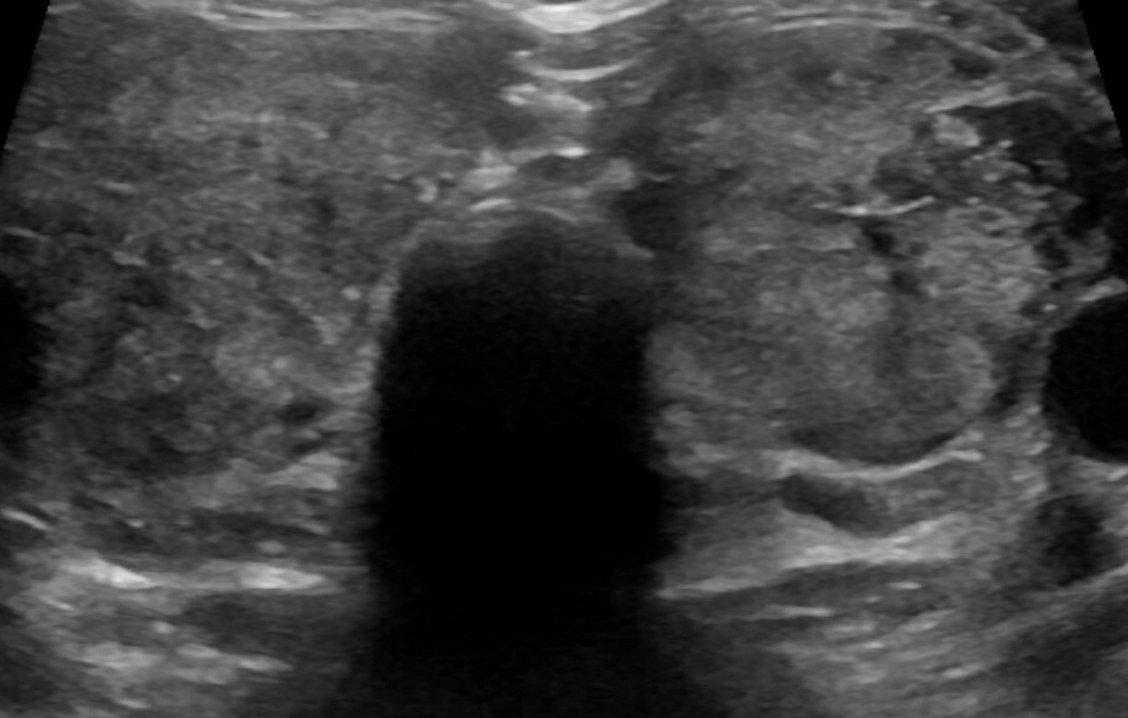

Graves' Disease

Autoimmune Disorder

Graves’ disease occurs when your child’s immune system develops antibodies that attach to the thyroid cells, causing them to produce too much thyroid hormone. This antibody, thyroid-stimulating immunoglobulin (TSI), binds to the thyroid-stimulating hormone (TSH) receptor and causes unregulated production and release of thyroid hormone.

Graves’ disease affects 1 in 10,000 children in the United States and is much less common than Hashimoto's thyroiditis. It is more common in girls than in boys.